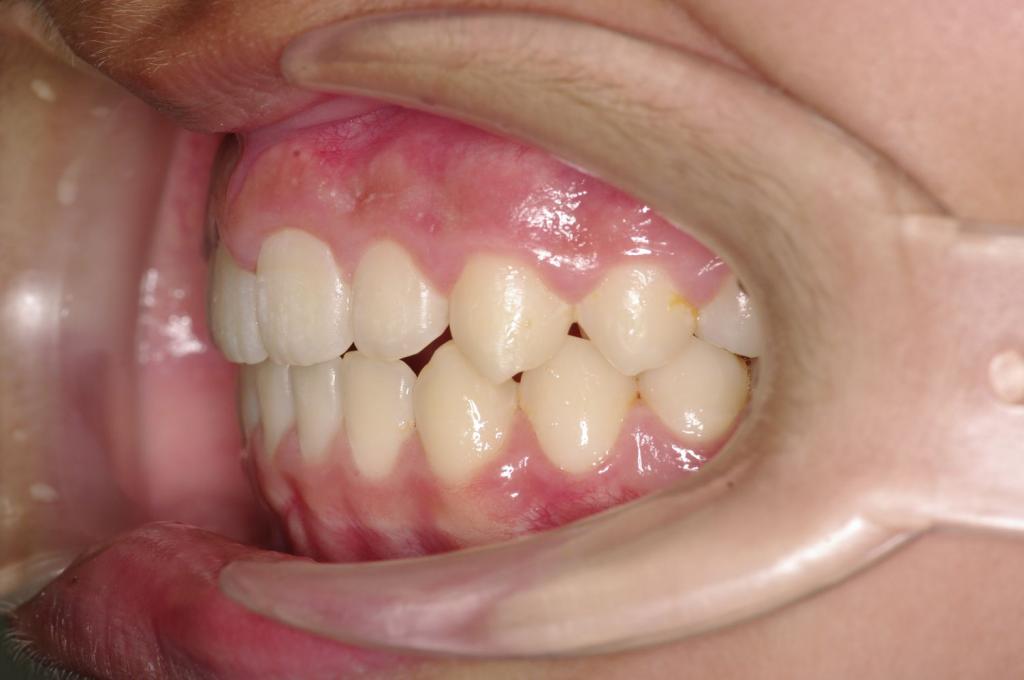

前歯、出っ歯・開咬の矯正治療

(治療期間、治療前後写真、治療方法、費用)WORKS